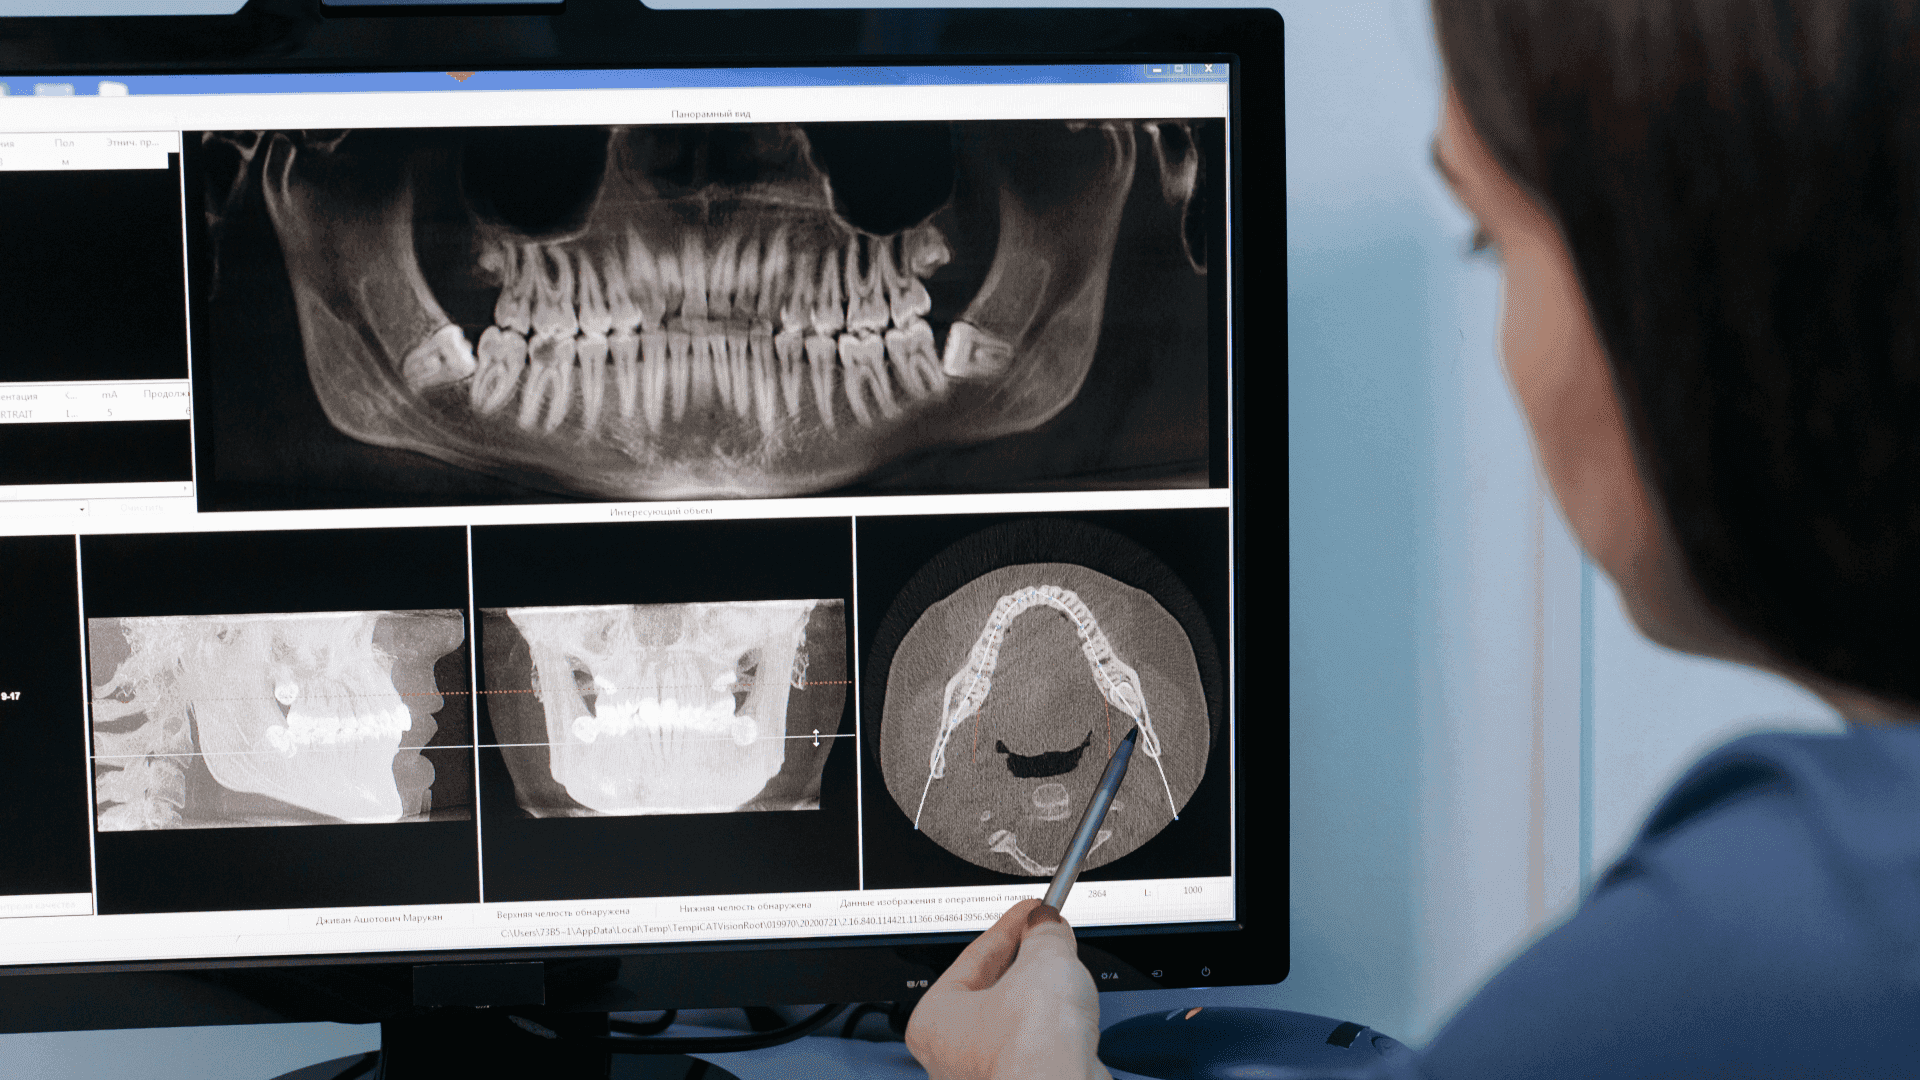

Tomografia stożkowa (CBCT) 5x5 to innowacyjna metoda diagnostyczna, oferująca niezrównaną precyzję w badaniach stomatologicznych i maxillofacjalnych. Format 5x5 cm odnosi się do pola widzenia urządzenia, idealnego do szczegółowej analizy pojedynczych obszarów, takich jak indywidualne zęby, korzenie czy określone sekcje szczęki i żuchwy. CBCT 5x5 jest szczególnie ceniona za swoją zdolność do uzyskiwania trójwymiarowych obrazów, co jest kluczowe w planowaniu leczenia implantologicznego, endodontycznego i ortodontycznego, zapewniając pełniejsze zrozumienie anatomii pacjenta.

Tomografia CBCT (Cone Beam Computed Tomography) 5x5 wykorzystuje specjalizowaną technologię stożkowego promienia rentgenowskiego, która obraca się wokół pacjenta, rejestrując setki pojedynczych obrazów z małego, precyzyjnie określonego obszaru. Te obrazy są następnie przetwarzane cyfrowo, tworząc dokładny, trójwymiarowy model badanego obszaru. Technologia ta zapewnia wyjątkową rozdzielczość obrazu przy znacznie niższych dawkach promieniowania niż tradycyjna tomografia komputerowa (CT), co czyni ją bezpieczniejszą dla pacjentów. CBCT 5x5 jest szczególnie przydatna w przypadkach, które wymagają wysokiej precyzji, jak ocena stanu zębów przed zabiegami endodontycznymi czy planowanie umieszczenia implantów.